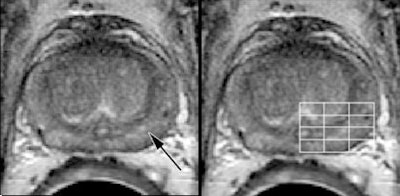

| A 60-year-old patient with biopsy-proven recurrent prostate cancer in the left side of prostate. Axial T2-weighted MR image (left) shows findings consistent with post-treatment changes (arrow). However, MR spectroscopic image (right) shows areas of malignant metabolism (line grid). Images courtesy of Radiology. |